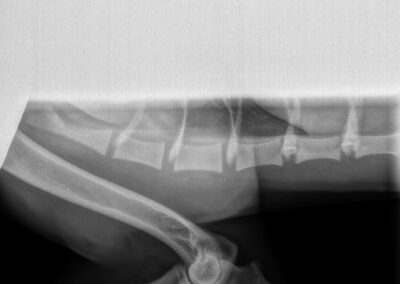

rug: 100% (foto’s aanwezig)